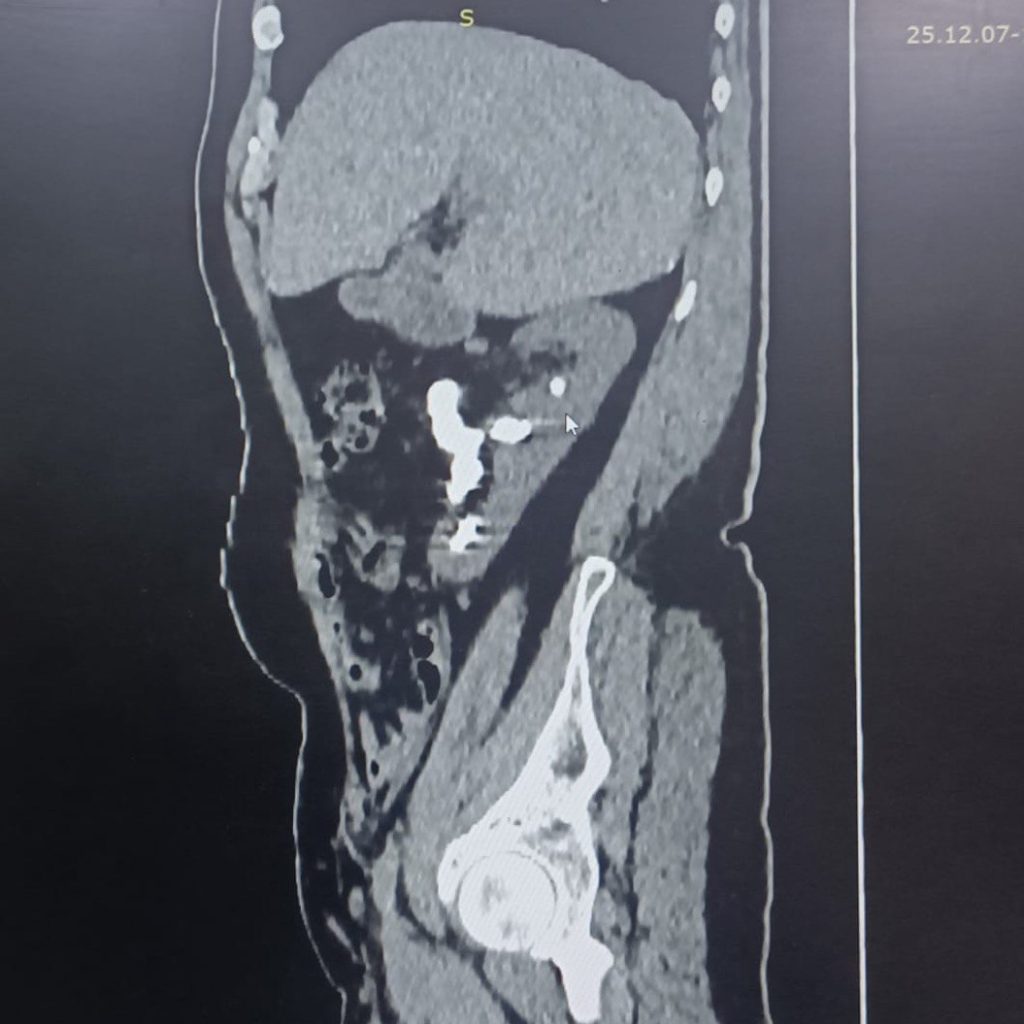

بعد معاناة امتدت لأكثر من خمس سنوات، وضع خلالها الألم الكلوي المزمن وآلام الظهر المريض أمام تحدٍّ يومي قاسٍ، نجح فريق طبي متخصص في مستشفى الإمام الحجة (عج) الخيري في طيّ صفحة واحدة من أعقد الحالات الكلوية، عبر إجراء عملية ناظورية متقدمة لاستخراج حصاة من نوع قرن الأيل تجاوز حجمها 10 سم.

«تمكّنا، بفضل الله، من إجراء عملية ناظورية حديثة عبر الجلد، استخرجنا خلالها الحصاة بالكامل من خلال فتحة صغيرة لا تتجاوز 1 سم، دون الحاجة إلى أي فتح جراحي، وهو ما خفف كثيرًا من المخاطر وساعد على تسريع التعافي».